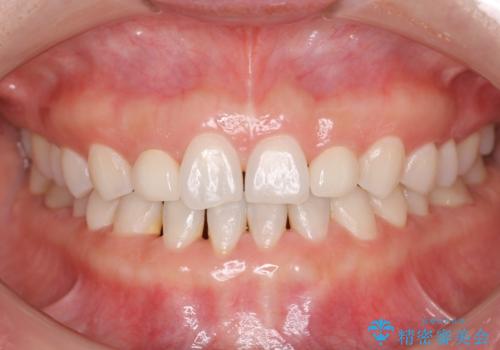

歯の形気になる!! セラミック治療 前歯( エクセレント)

- 歯の形が気になるということで以前入っていたプラスチックのものから、セラミックでの治療を希望されたので行いました。

色や形をこだわりたいということで、当院最上位ランクのエクセレントにて治療を行いました。

以前使用していた被せ物を除去して、仮歯に置き換えます。

その後、歯の最終的な形を作って型取りを行います。

当院で患者様の口腔内の写真を撮影し技工士さんに指示を出して完成します。

患者様はかなり喜ばれておりました。